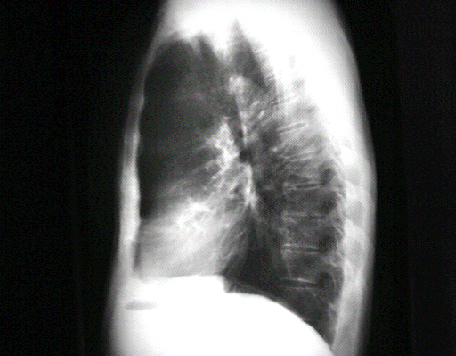

Lateral

This chest X ray shows a

calcified aortic valve

. The lateral view is often best for demonstrating such a finding.